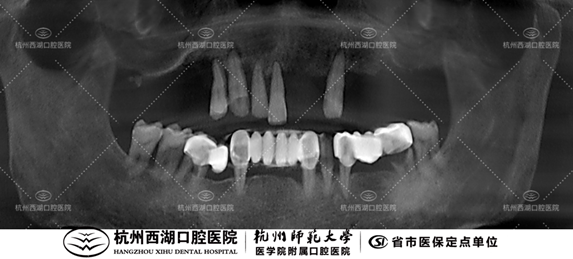

术前CBCT照如下

检查:牙列缺损,慢性牙周炎

医生建议:拔除上颌剩余牙齿,全口即刻修复 all-on-6